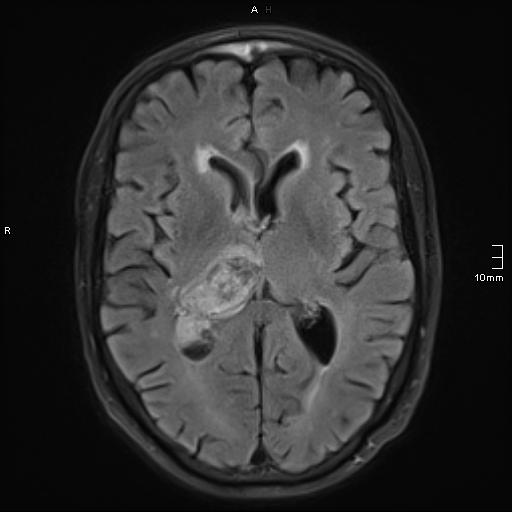

Note the multiple sites of oedema and haemorrhage, involving the brain stem and corpus callosum as well as subcortical white matter and left cerebral peduncle. High FLAIR signal is also seen in the dorsal midbrain. EVD insitu.

Case Discussion

Diffuse axonal injury can be subtle on CT but have devastating consequences for the patient. This is a case of grade III injury (involvement of brainstem) and carries a poor prognosis.

Diffuse axonal injury

Dr Jay Gajera◉ and Assoc Prof Frank Gaillard◉◈ et al.

Diffuse axonal injury (DAI), also known as traumatic axonal injury (TAI), is a severe form of traumatic brain injury due to shearing forces. It is a potentially difficult diagnosis to make on imaging alone, especially on CT as the finding can be subtle, however, it has the potential to result in severe neurological impairment.

The diagnosis is best made on MRI where it is characterised by several small regions of susceptibility artifact at the grey-white matter junction, in the corpus callosum, and in more severe cases in the brainstem, surrounded by FLAIR hyperintensity.

Diffuse axonal injury is characterised by multiple focal lesions with a characteristic distribution: typically located at the grey-white matter junction, in the corpus callosum and in more severe cases in the brainstem (see: grading of diffuse axonal injury).

The appearance depends on whether or not the lesions are overtly haemorrhagic. Haemorrhagic lesions will be hyperdense and range in size from a few millimetres to a few centimetres in diameter. Non-haemorrhagic lesions are hypodense. They typically become more evident over the first few days as oedema develops around them. They may be associated with significant and disproportionate cerebral swelling.

CT is particularly insensitive to non-haemorrhagic lesions (as defined by CT) only able to detect 19% of such lesions, compared to 92% using T2 weighted imaging 4. When lesions are haemorrhagic, and especially when they are large, then CT is quite sensitive. As such, it is usually a safe assumption that if a couple of small haemorrhagic lesions are visible on CT, the degree of damage is much greater.

MRI

MRI is the modality of choice for assessing suspected diffuse axonal injury even in patients with entirely normal CT of the brain 5,6. MRI, especially SWI or GRE sequences, exquisitely sensitive to paramagnetic blood products may demonstrate small regions of susceptibility artefact at the grey-white matter junction, in the corpus callosum or the brain stem. Some lesions may be entirely non-haemorrhagic (even using high field strength SWI sequences). These will, however, be visible as regions of high FLAIR signal.